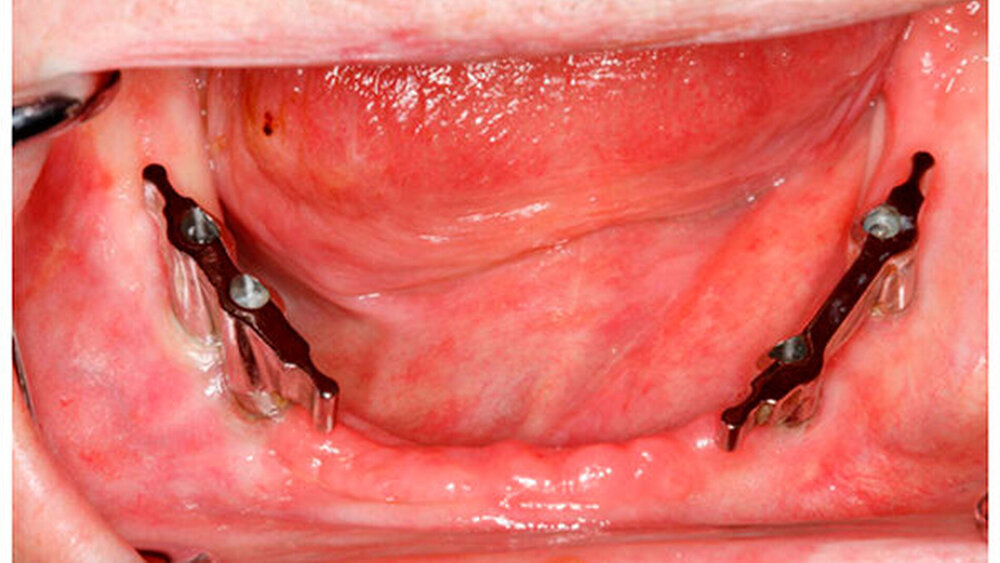

Nach einem Jahr Tumorfreiheit konnte dann die zahnmedizinische Rehabilitation beginnen: Hierzu wurden jeweils vier Implantate gesetzt, im Oberkiefer erfolgte ein zusätzlicher Kieferknochenaufbau. Nach der problemlos verlaufenden Einheilphase konnten der aus dem Labor angefertigte Steg und die endgültige prothetische Versorgung des Ober- und Unterkiefers eingesetzt werden.